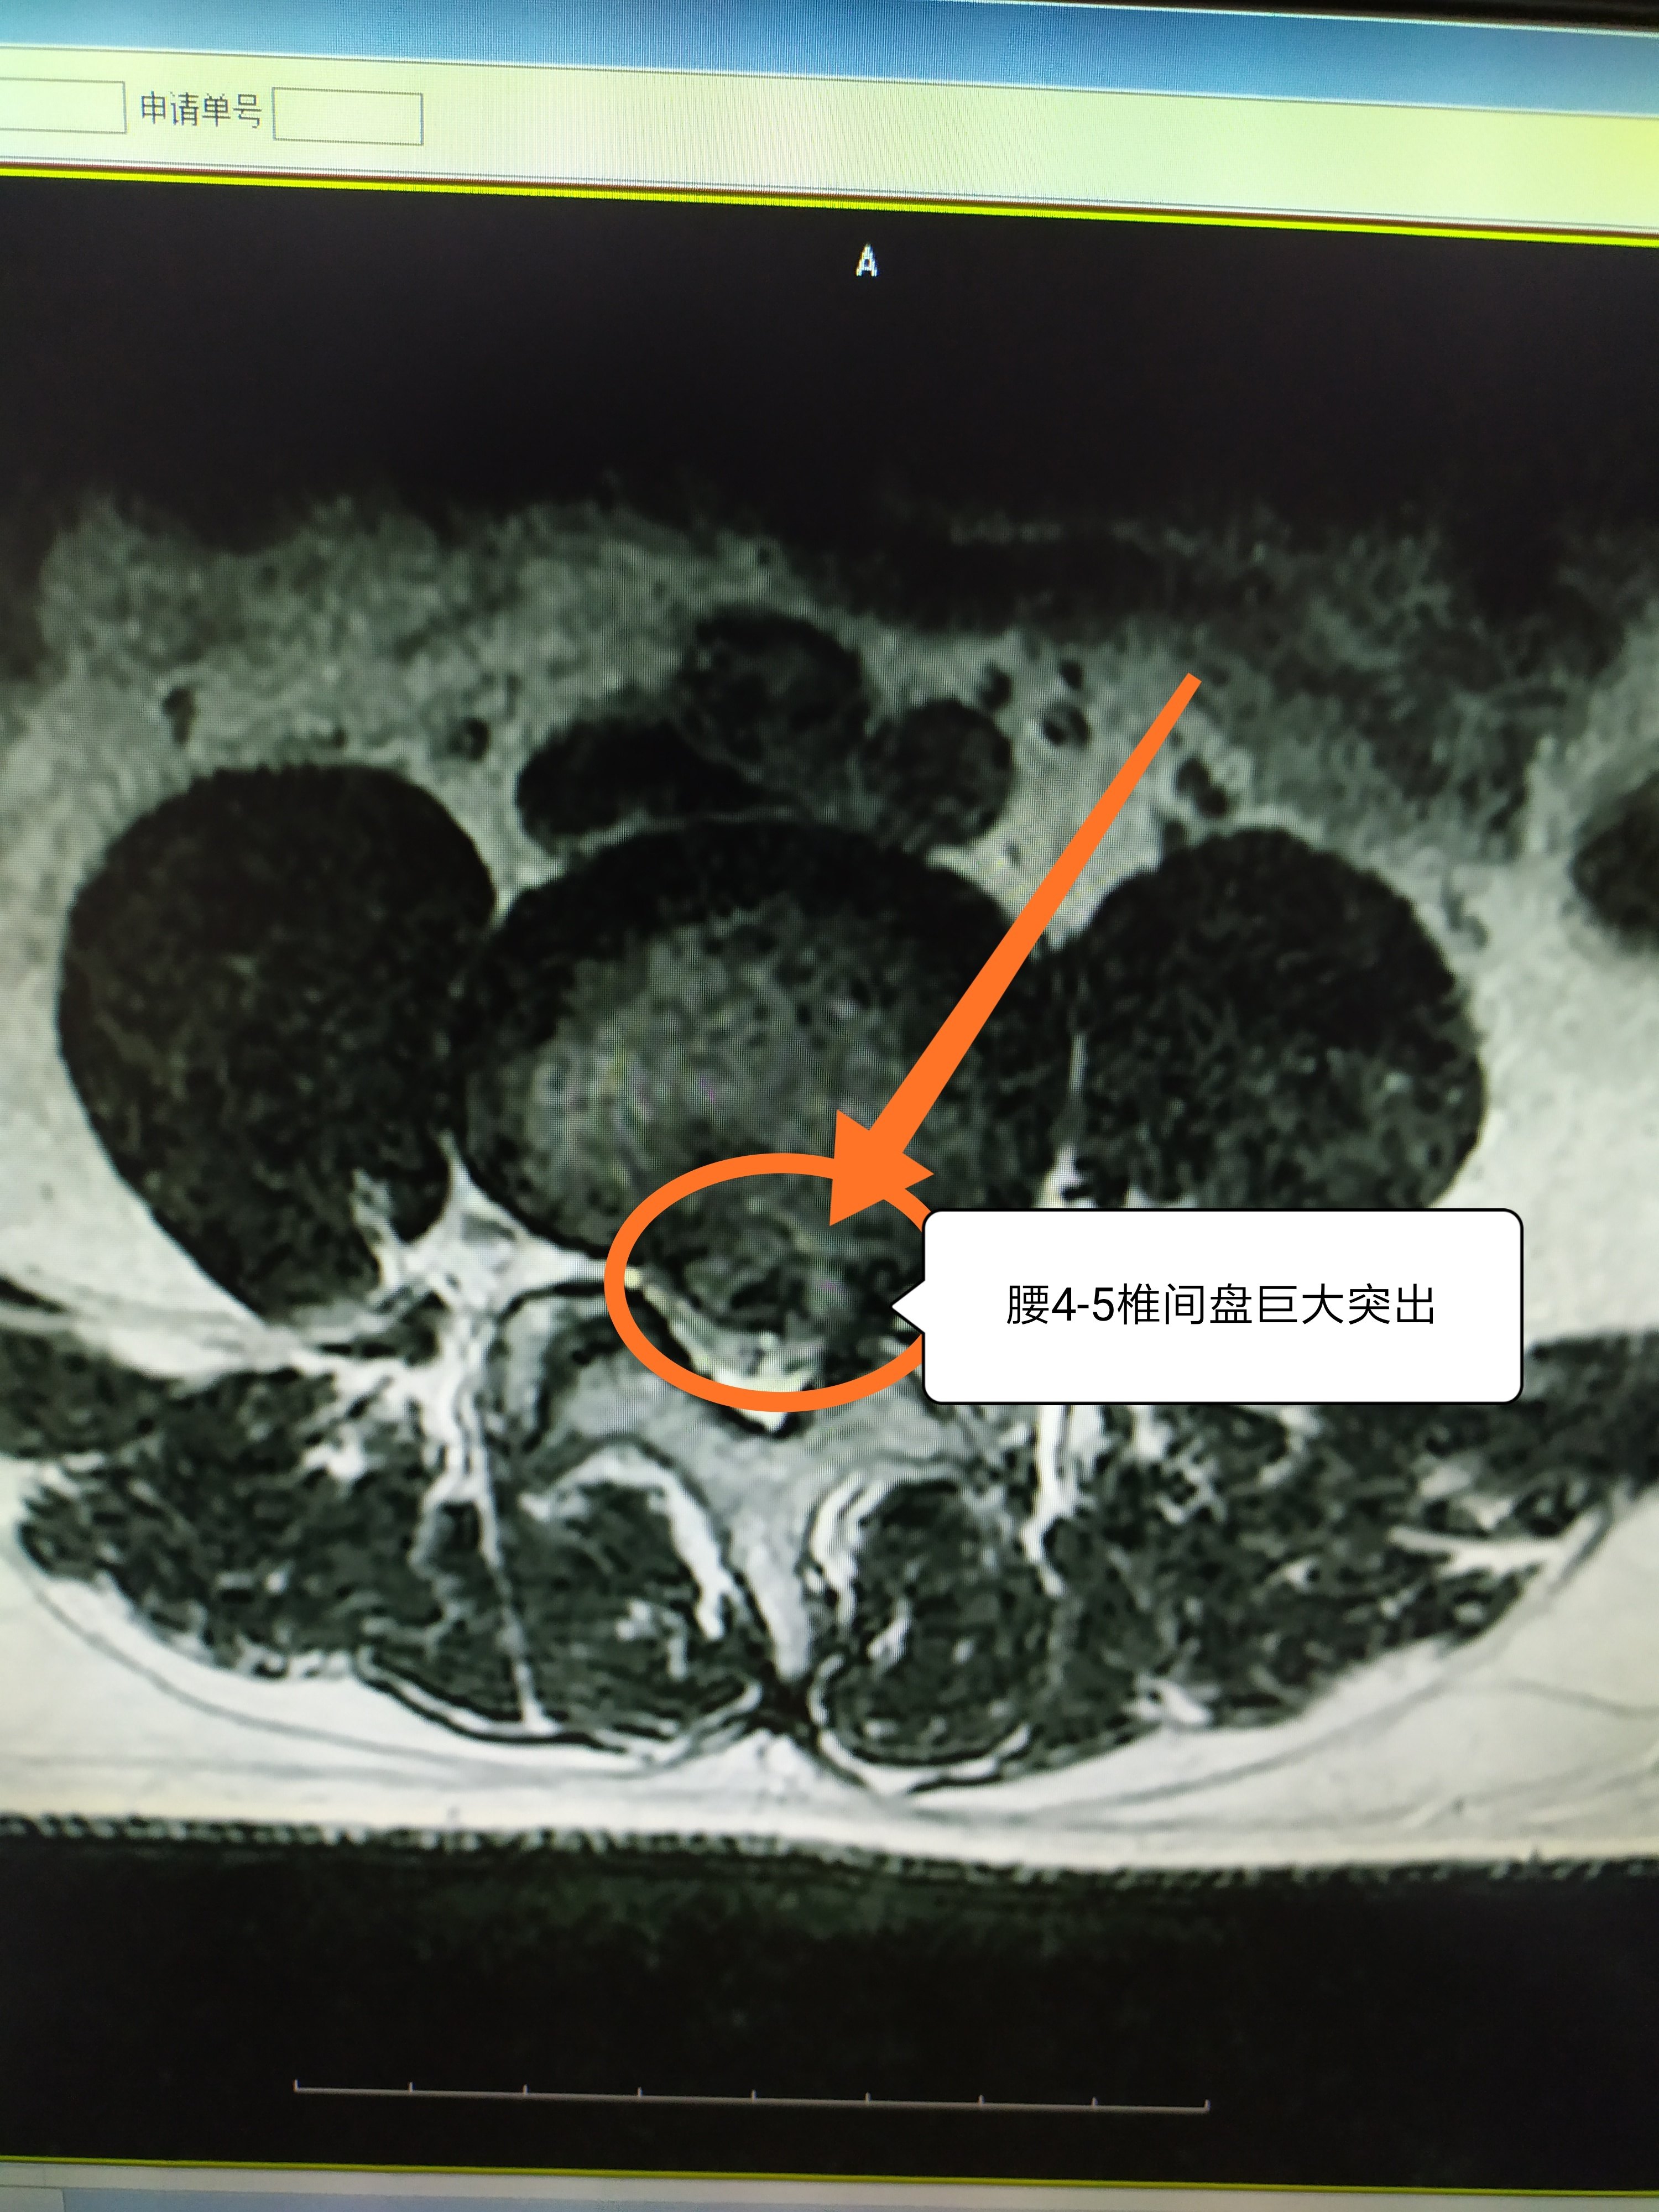

MRI检查对椎间盘突出症的诊断具有重要意义。通过不同层面的矢状面影像及所累及椎间盘的多方位影像,可以观察病变椎间盘突出的形态及其与周围组织的关系。

核磁共振成像技术(即MRI)是对于软组织(椎间盘突出部位、方向,脊髓神经根受压情况)检查方法,除了临床病史和体格检查,MRI已经是诊断腰椎间盘突出症的常用检查方法。